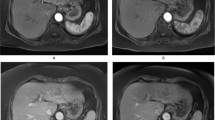

Before OXi4503 delivery, tumours displayed variable baseline measurements of perfusion and R2*, with a heterogeneous spatial distribution for each parameter within each tumour. Following treatment with OXi4503, a heterogeneous response was observed in both tumour types by ASL and IS-MRI techniques, as can be seen in the example maps shown in Figure 2A. Absolute and relative changes from baseline in perfusion and R2* measurements across groups are shown in Table 1, with normal appearing liver from the same animals included as an internal control; a significant decrease in perfusion was detected in SW1222 metastases for both treated and saline control groups. The decrease in perfusion of the saline control group is not fully understood, though actual perfusion change is small, it is potentially due to minor dehydration caused by prolonged imaging (Ramasawmy et al, 2014). No significant change was measured in treated LS174T tumours, probably due to their low levels of baseline perfusion. Perfusion in normal-appearing liver tissue was varied, although it decreased non-significantly across the groups.

Functional response of the tumour vasculature to disruption with OXi4503. Example high-resolution, axial images (A) with perfusion (top row) and R2* (bottom row) maps overlaid on tumour ROIs (SW1222 on the left, and LS174T on the right, pre- and post OXi4503 therapy). A heterogeneous spatial distribution can be seen in both parameters, both within individual tumour deposits and across different tumours within the same liver. Histological staining by H&E is shown for saline control (B), and OXi4503-dosed SW1222 (C) and LS174T (D) tumours. The arrows highlight the centre of liver tumour deposits (B, viable and C and D, necrotic).

For change in R2* the only significant change measured was within the VDA-treated LS174T tumours, with no significant changes observed in the SW1222 tumours (treated and control) or normal-appearing liver. Histological assessment of tumour metastases viability by H&E staining shows that saline-dosed control SW1222 tumours (Figure 2B) are highly nucleated and viable, with little areas of necrosis, while both OXi4503-treated SW1222 (Figure 2C) and LS174T (Figure 2D) tumours have large central necrosis with a small rim of surviving tumour cells surrounding the metastasis. No change was observed in the surrounding normal liver tissue.